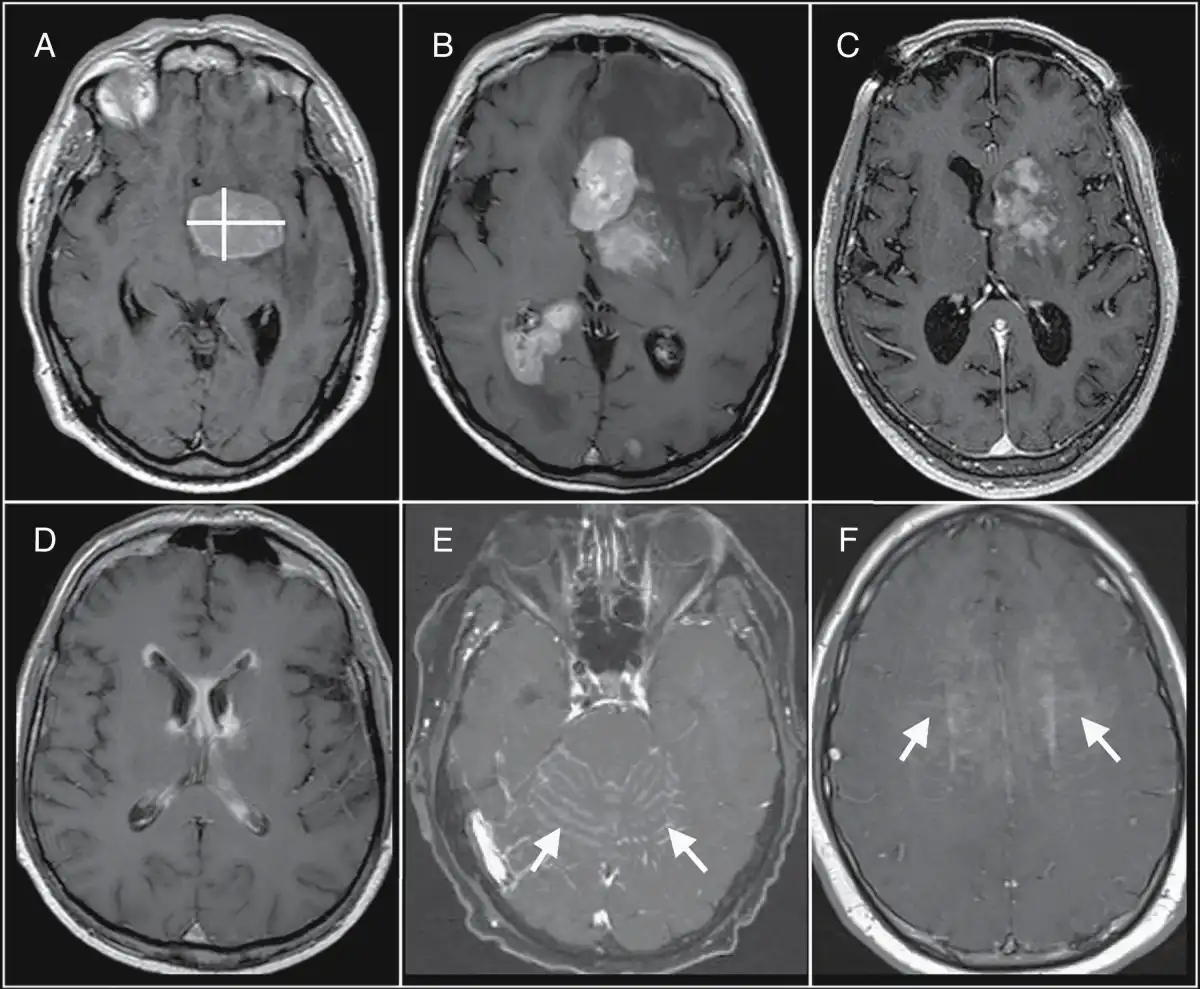

—At initial diagnosis, PCNSL in immunocompetent hosts classically demonstrates avidly enhancing lesions (up to 60%-75% of which are multiple). Most are supratentorial (80%), in a periventricular or deep cerebral white matter distribution. As shown in Figure 2, both morphology and multiplicity of MRI-enhancing lesions can present difficulties in applying conventional two-dimensional (2D) sum product measurements, both in regard to labor intensiveness and inter-user variability. This can present challenges for reliably defining simple and reproducible measures of tumor burden at baseline, and response assessment based on serial imaging. In this way, the volumetric analysis would help to automate measurements of tumor burden, with improved precision and clinical applicability.,

Fig. 2

Challenges of bidirectional measurements of primary central nervous system lymphoma (PCNSL) tumor burden. (A) A single-rounded PCNSL mass lends itself to straightforward bidirectional measurement (yellow lines). (B) These bidirectional measurements can also be applied to multiple discrete masses. However, bidirectional measurements become more challenging with varied imaging patterns, such as with (C) heterogeneous enhancement, (D) linear ependymal enhancement, (E) leptomeningeal enhancement (arrows), and (F) linear perivascular enhancement (arrows). These varied imaging patterns would be more amenable to measurement using volumetric-based approaches to define tumor burden. Abbreviations: ADC, apparent diffusion coefficient; CBV, cerebral blood volume; DCE, dynamic contrast-enhanced; DSC, dynamic susceptibility contrast; PCNSL, primary central nervous system lymphoma.